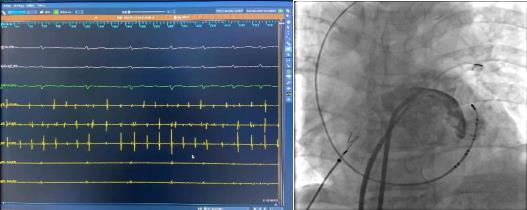

術(shù)前腔內(nèi)電圖可見(jiàn)毫無(wú)規(guī)律的房顫波,接著穿刺房間隔建立左房通路。完成肺靜脈隔離及頂部線消融后房顫轉(zhuǎn)復(fù)為規(guī)律的心房撲動(dòng)。

Marshall靜脈酒精消融完成后進(jìn)行左房標(biāo)測(cè)提示二尖瓣峽部徹底隔離,酒精消融成功,接著進(jìn)行三尖瓣峽部消融后患者房撲轉(zhuǎn)為竇性心律,完美完成此次房顫的消融手術(shù)。